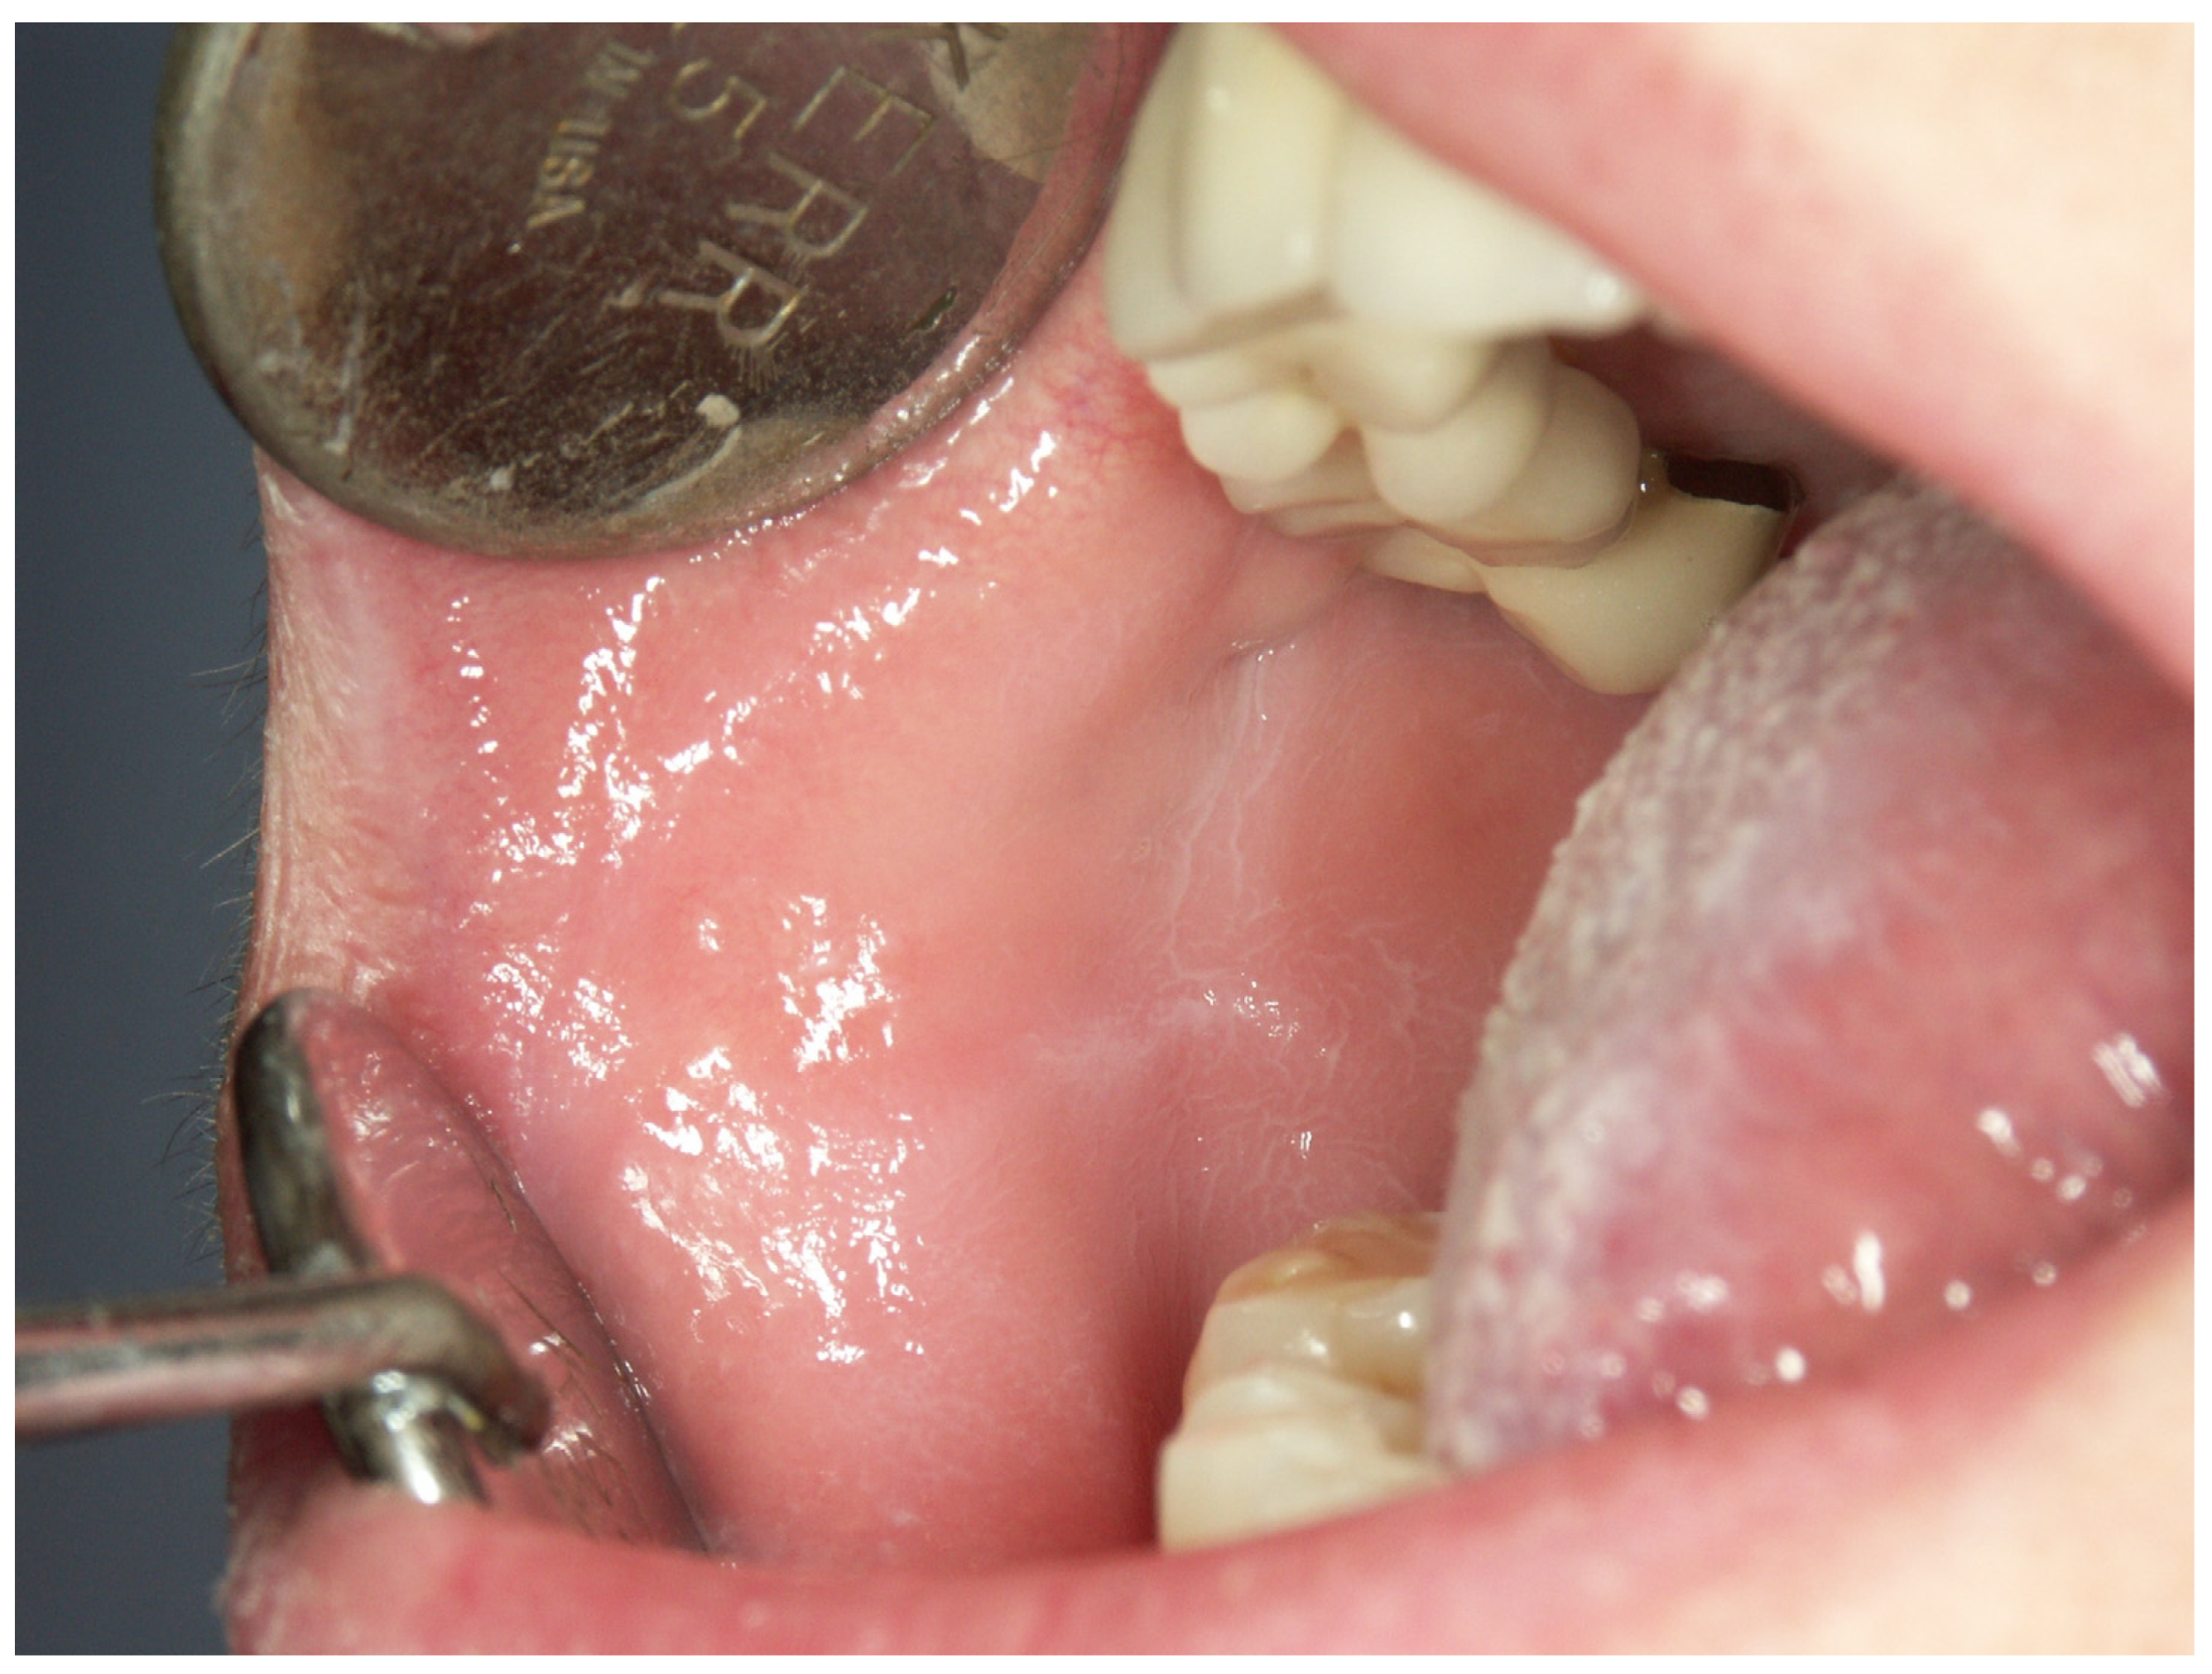

Appendix A. Clinical Presentation of OPMD

General Principles of Treatment of the Main OPMDs